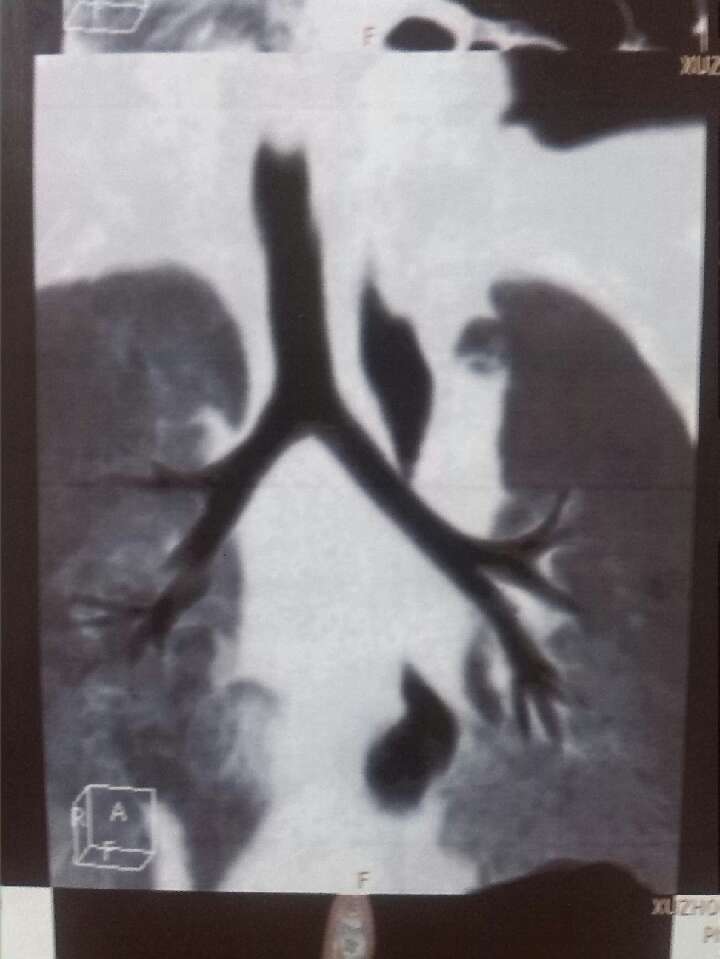

婴儿出生50天,先天性喉喘鸣,喉软骨软化,喉部气管软化,呼吸困难,肺炎,怎么治,能治好吗?推荐医院 救命啊,小孩先天性喉喘鸣,喉软骨软化,喉部气管软化,呼吸困难,肺炎,该怎么治,能治好吗? 点击展开 匿名用户 2013-12-08 10:14 为您推荐: 其他回答 建议到省立儿童医院就医——完全可以解决。 贾骊英_l1dy 2014-10-07 13:53 相关问题 俩月宝宝先天性喉骨软化加重症支气管肺炎 早产四斤多低血钙,肺炎,气管软化怎么办 我小孩今年11岁,5月份时得了支气管肺炎,住院14天,开始是咳嗽严重,呼吸困难,低烧 第7-8天时,就不咳